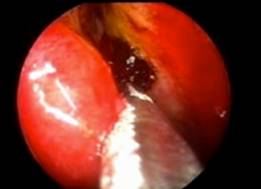

![]() |

| Endonasal DCR | |